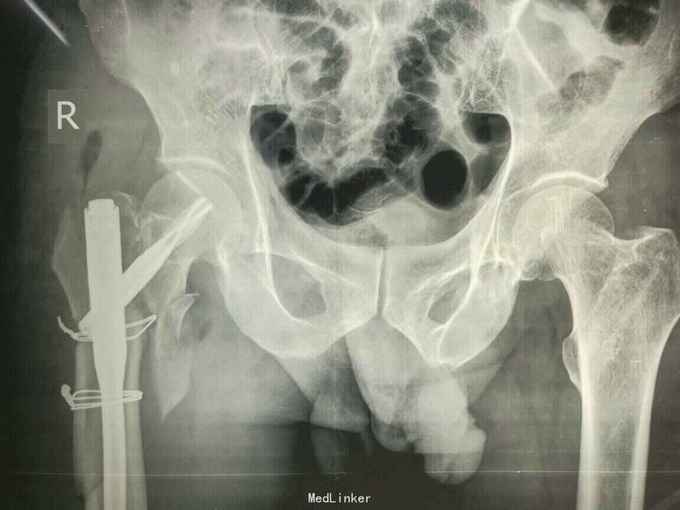

主诉:外伤后右大腿及右髋部疼痛,活动受限2小时 病史:患者自述于2小时前从高处摔伤右下肢及右手,伤后感右髋部右下肢及右手疼痛,活动受限,不能站起行走。自述未伤及头部。由家人送往我院诊治,经详细查体后以“右股骨骨折,右粗隆间骨折,右舟骨骨折”收入院。患者自入院以来精神状态尚可,未进食水,未排二便。

查体:右大腿皮肤无破损,大腿上段及右髋部软组织肿胀,未见皮下淤斑,右髋部及股骨近端环形压痛,局部可触及骨擦感及异常活动,右下肢纵向叩击痛阳性,肢端感觉良好,足背动脉可触及。右手近腕关节处肿胀,舟骨处压痛阳性,叩击痛阳性,右腕关节活动受限。 辅助检查:右髋及大腿x线示右股骨转子间粉碎骨折,对位对线尚可,右股骨干粉碎骨折,对位对线差,右手dr片右舟骨骨折,位置良好。

诊断:右股骨转子间骨折 右股骨干骨折 治疗:切开复位髓内钉固定术